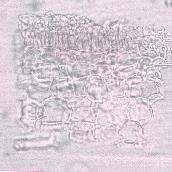

b) Hypodermal cells

- (b) A fragment of the leaf showing a portion of the hypodermal cells (top left) containing yellowish pigments underlain by cylindrical palisade cells followed by cleared semi-rounded spongy mesophyll cells.